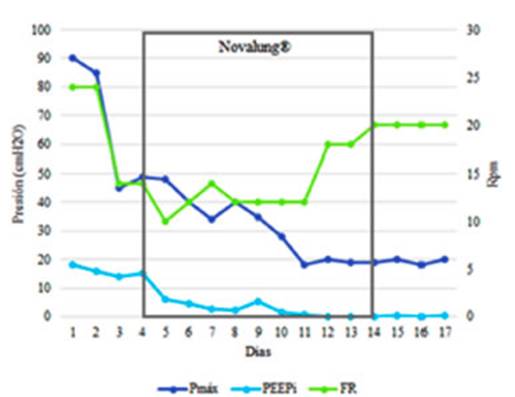

muestran en la Tabla 1. Veinticuatro horas después de la conexión

a Novalung®️,

la presión máxima (Pmáx) de las

vías respiratorias se redujo y la oxigenación permaneció

sin cambios. Las modificaciones más importantes fueron la caída

de la PEEPi y de la Pmáx

(Figura 1).

El

principal hallazgo fue identificar la potencia mecánica resistiva como

el principal responsable del brotrauma en un paciente

con EA. Se observó una notable correlación entre el PEEPi y la Pmáx de la

vía aérea, las que disminuyeron drásticamenÂte cuando

logramos bajar la FR, reducir el VT

y prolongar el tiempo espiratorio (relación I:E = 1:7) después de instalar el Novalung®.

Luego de introducir este dispositivo se pudo reducir la FR de 24

rpm a 10 rpm, con lo cual la PEEPi se redujo de 15

cmH2O a 6 cmH2O.